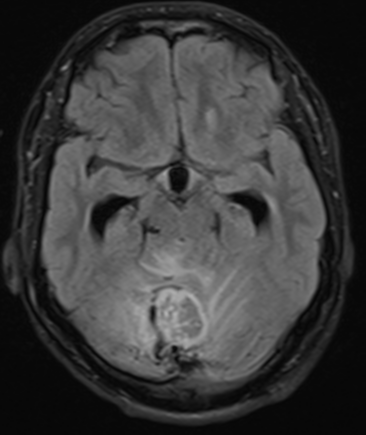

1 — RM de encéfalo com contraste

- Pós-contraste: T1 multiplanar (axial, coronal, sagital) com cobertura da fossa posterior.

- Cérebro e medula espinhal: RM com e sem contraste, cortes finos via 1.5 T, frequência a cada 12-24 meses :contentReference[oaicite:2]{index=2}.